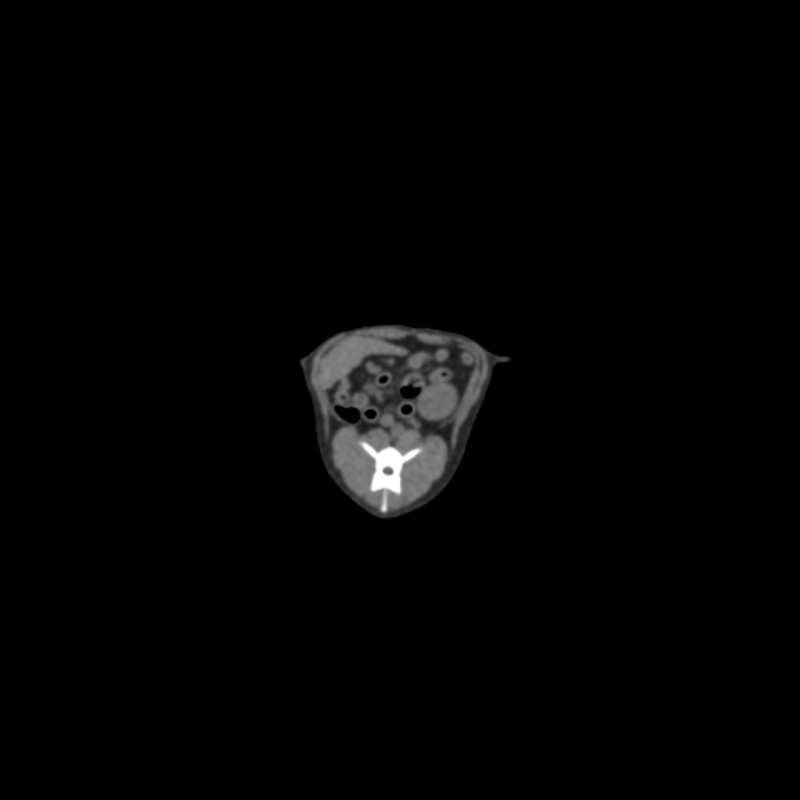

Fantom zagotavlja realistično simulacijo psa brez kontrastnega sredstva. Kosti in mehka tkiva so prikazana verodostojno z realističnimi vrednostmi CT za vsa tkiva pri 120 kVp napetosti cevi v CT. Zračni prostori so zapolnjeni s celuloznim polimernim kompozitom s približno -80 Hounsfieldovimi enotami.

Če se bo fantom uporabljal predvsem pri drugih napetostih cevi (npr. 100 kVp), se lahko po potrebi ustrezno prilagodi kalibracija vrednosti CT ? Fantom zagotavlja tudi realistične kontraste tkiv pri rentgenskem slikanju.

Velikost: 26x15x80 cm